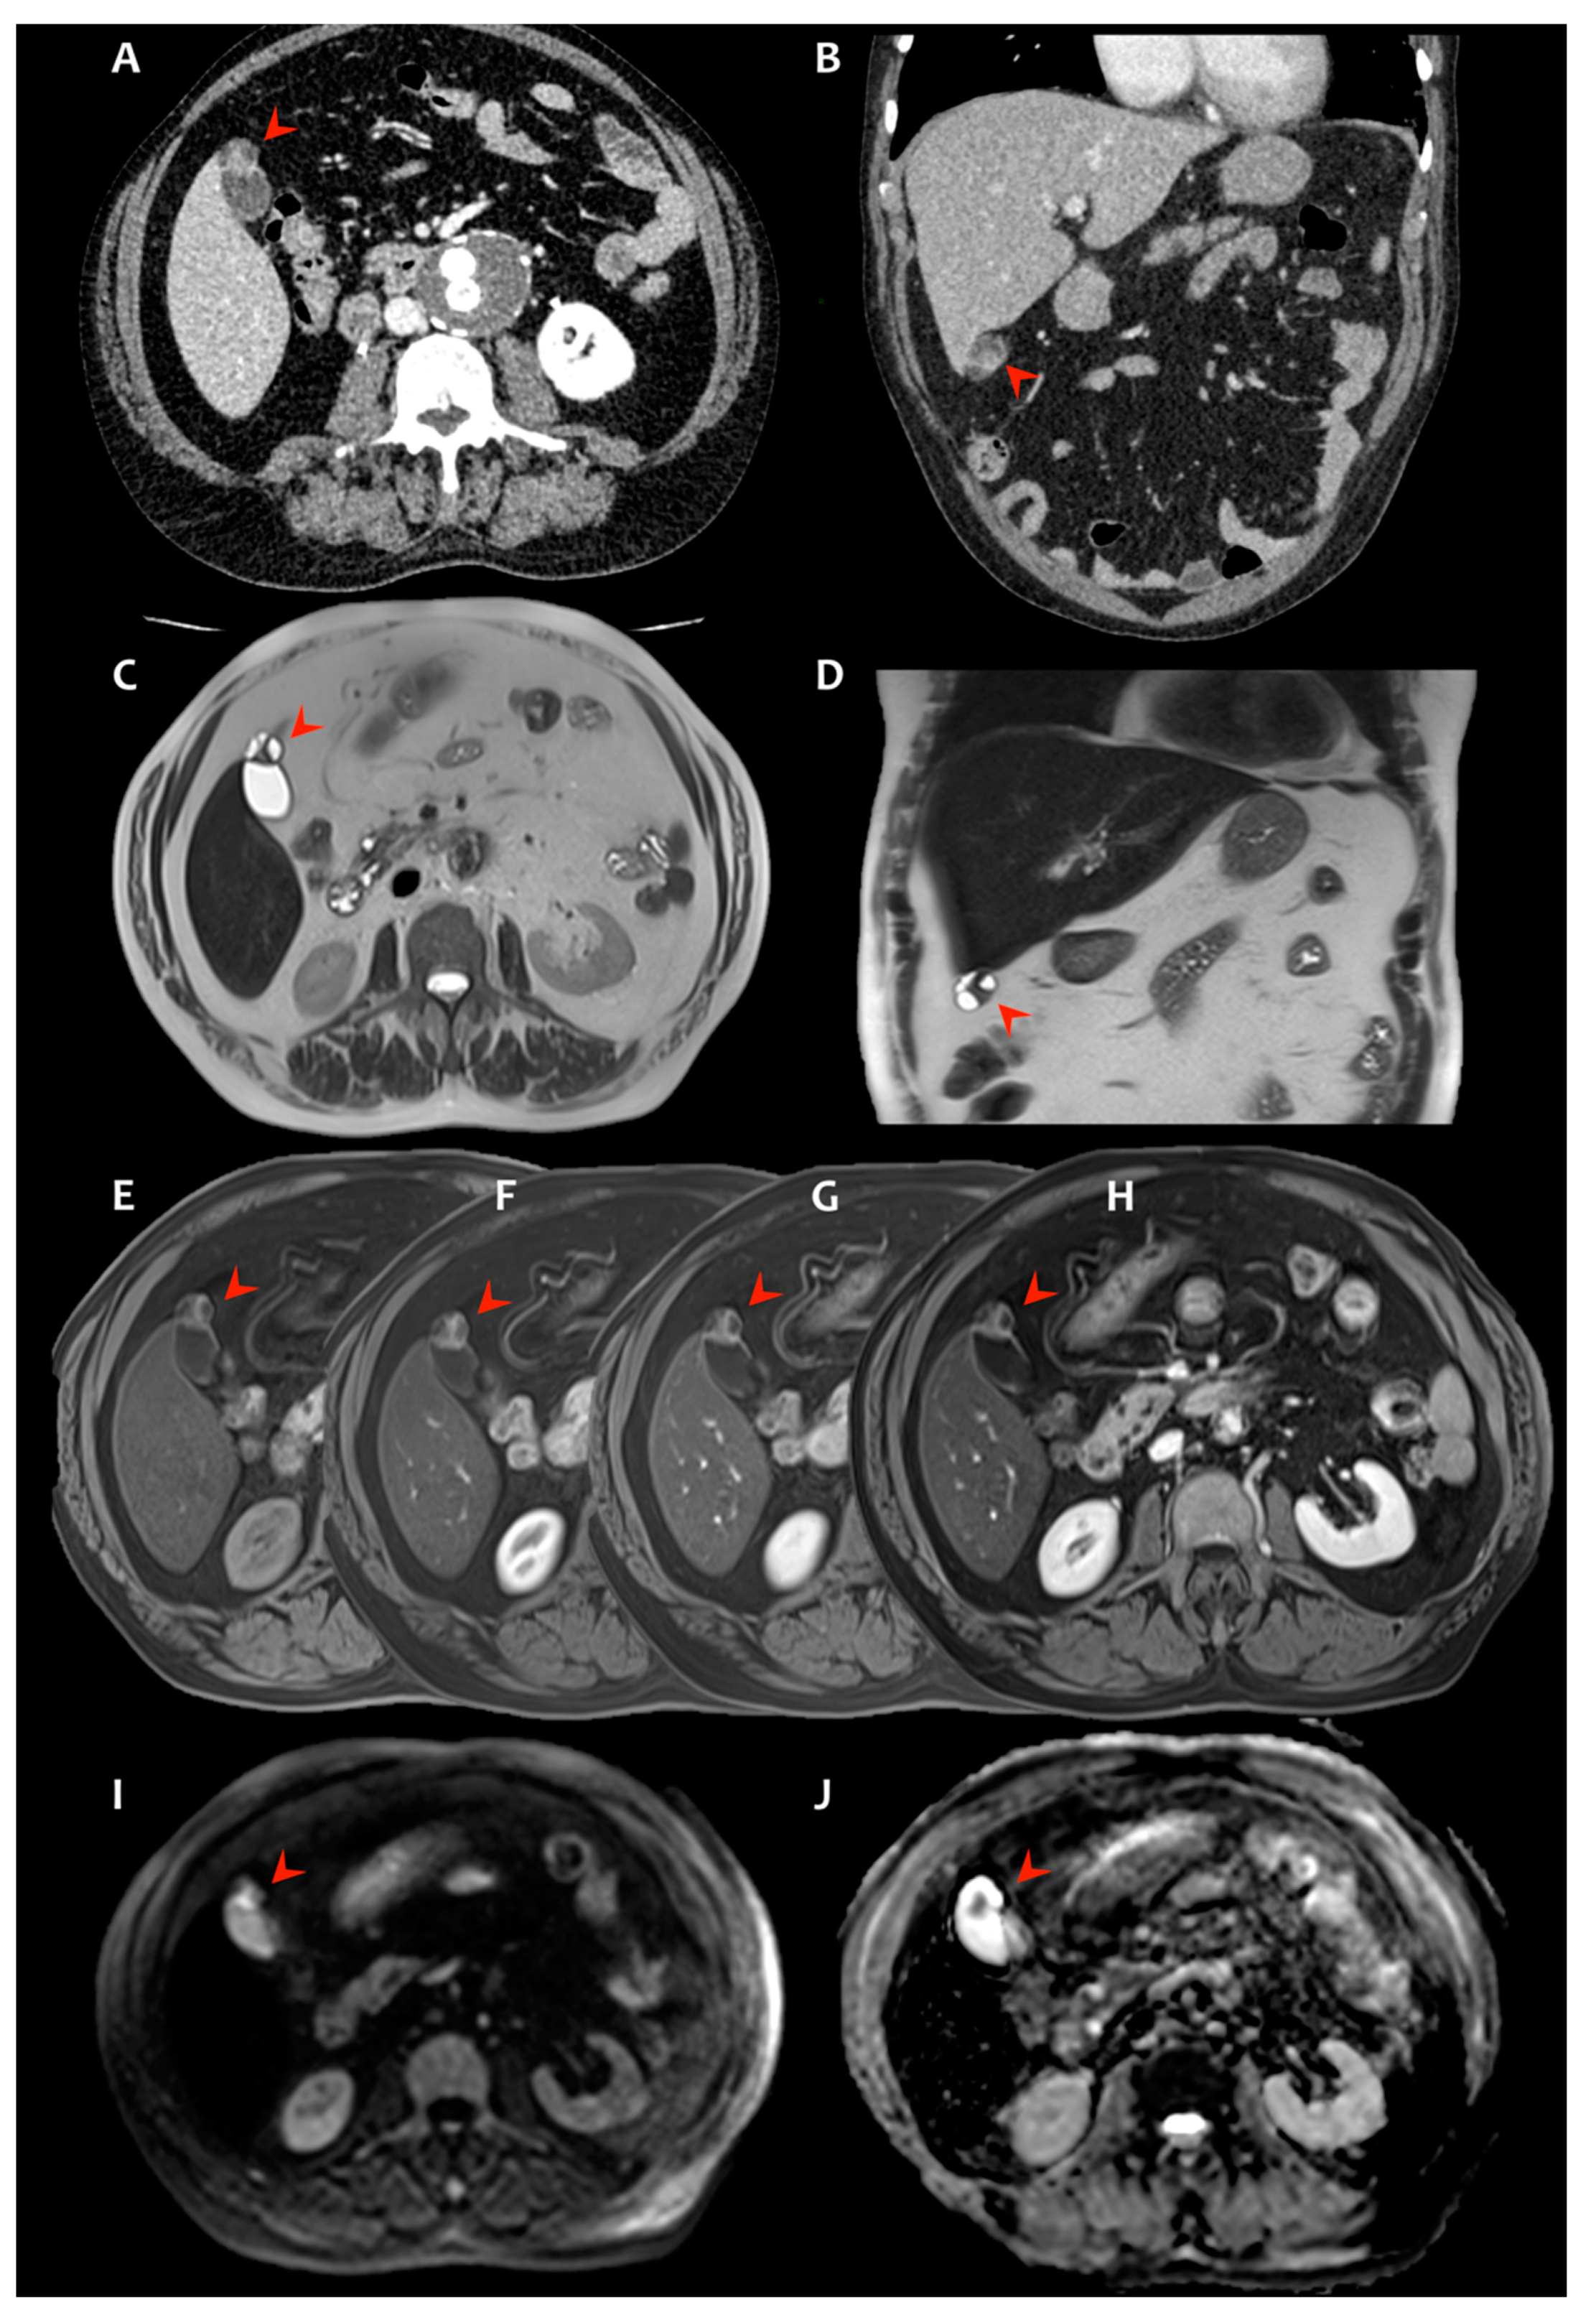

2. Presentation of Case #1